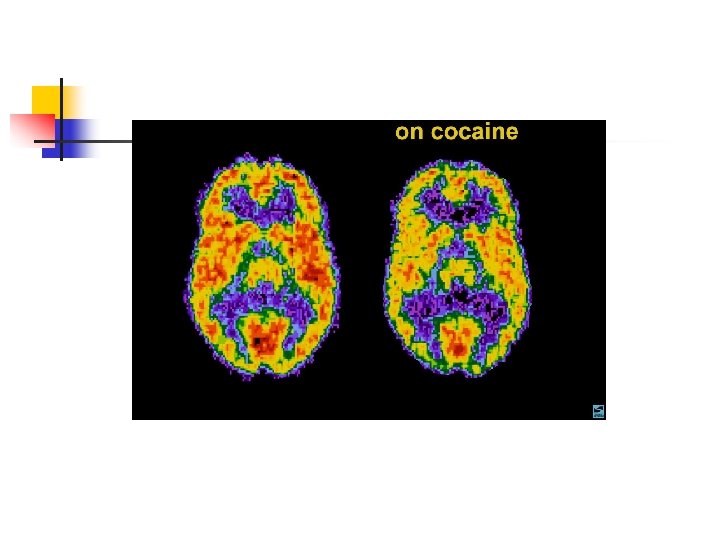

ANFETAMINAS E COCAÍNA EFEITOS CEREBRAIS: ATIVA OS SISTEMAS DOPAMINÉRGOS MESOLÍMBICOS E MESOCORTICAIS, INIBINDO A RECAPTAÇÃO DE DOPAMINA NOS TERMINAIS SINÁPTICOS E PROMOVENDO SUA LIBERAÇÃO NAS SINAPSES.

ANFETAMINAS E COCAÍNA EFEITOS COMPORTAMENTAIS 1 - LOQUACIDADE 2 -INQUIETAÇÃO 3 - ANGÚSTIA 4 -IRRITABILIDADE 5 - CONFUSÃO MENTAL 6 - ALUCINAÇÕES